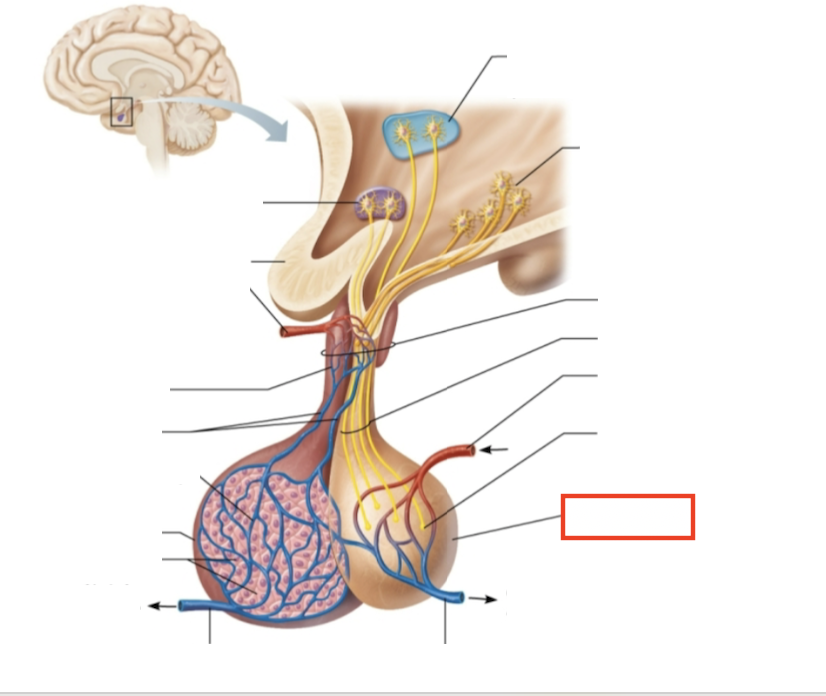

What structure is highlighted?

testes (male)

What are the target organs and effects of testosterone?

most cells of the body; promotes the maturation of the male reproductive organs, the development of secondary sex characteristics, sperm production, and sex drive

What hormone is produced by the testes?

testosterone

What stimulates testosterone production?

LH and FSH